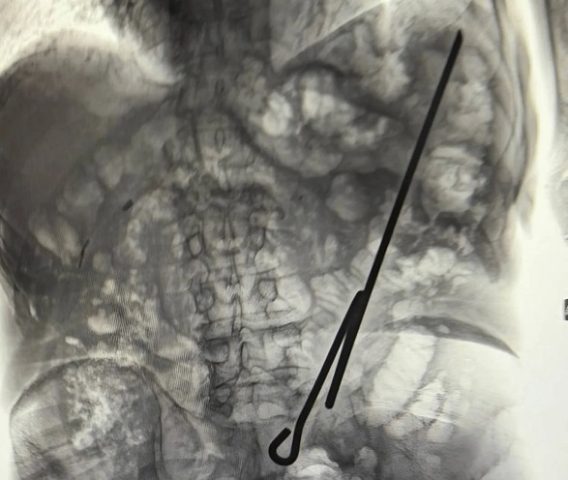

84-летний мужчина упал и напоролся на самодельный инструмент, которым и проводил работы. После этого пенсионера доставили в больницу, где врачи сделали все необходимые исследования. Пожилому мужчине потребовалась операция: извлекать инструмент пришлось хирургическим путём. К счастью, ни один орган брюшной полости не был задет. Сыграло роль и то, что пациент был голоден. По состоянию на 8 февраля пенсионера выписали.